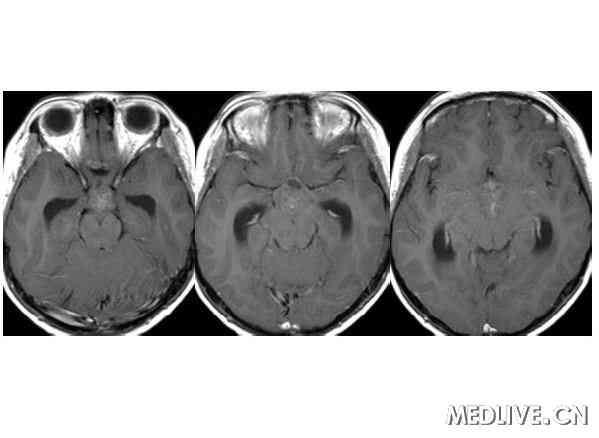

经典病例: 男性,15岁,身材发育迟缓,多饮多尿3年身材矮小

男性,15岁,身材发育迟缓,多饮多尿3年身材矮小 病理症阴性

鞍区生殖细胞瘤临床症状:多饮多尿,视力障碍 身材矮小,性早熟。

解答详情: 生殖细胞瘤由原始的生殖细胞衍生而来,好发于松果体区,其次为鞍上池。肿瘤多发生于男性青少年,位于鞍上生殖细胞瘤则以女性多见。生殖细胞瘤对放射线非常敏感。该瘤通常无包膜、无钙化、出血、坏死或囊性变,属低度恶性肿瘤,多呈浸润性生长,常有不同程度和形式的转移,易向蛛网膜下腔及脑室系统种植、播散。组织学上,肿瘤主要含有两种细胞成分:上皮样细胞和淋巴样细胞。 1、CT表现:  ①肿瘤最常见于松果体区,位于鞍上区肿块常累及漏斗;  ②CT平扫多呈等密度或稍高密度肿块,无出血、坏死及囊性变,可分叶,但境界清楚;瘤体本身钙化少见,典型松果体区生殖细胞瘤常见肿瘤包埋松果体钙化灶。  ③增强扫描呈中等至明显的均匀强化。  ④室管膜下转移可表现为沿脑室壁线状或条片状强化,沿脑脊液向蛛网膜下腔播散表现为脑表面、脑池的线状或结节状强化。   2、MR表现:  ①最常见于松果体区,也常见于鞍上,可同时或单独存在。②T1加权为略低信号或等信号,T2加权常呈等信号或高信号。③增强后;呈明显均匀一致强化,并能发现沿脑脊液或室管膜转移的病灶。鉴别诊断  1、颅咽管瘤:多为囊性或囊实性肿块,钙化多见。纯实性者可呈稍高密度,并可强化,与生殖细胞瘤不易鉴别、  2、星形细胞瘤:一般肿瘤较大,密度偏低,后期可出血,肿瘤通常位于下丘脑,并沿视交叉或视束延伸,可在眼眶内形成肿块。  3、垂体瘤:发生于鞍内,但可向鞍上生长,小儿罕见,肿瘤易出血、坏死,鞍底骨质变薄、下陷,海绵窦常受累。 生殖细胞瘤。4、脑膜瘤:好发于成人,儿童罕见,肿瘤部位偏前,伴骨质增生、硬化及蝶窦过度气化。